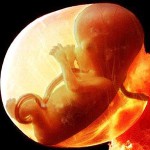

Voici à quoi ressemble le fœtus à la semaine 11 (cliquable):

L'enfant entier a maintenant la taille de la chaux. La longueur du corps est de 44 à 60 mm et le poids est d'environ 8 g.

Tous les organes et systèmes de l'enfant sont déjà formés. Ils sont dans un état différent. Par exemple, un petit cœur bat longtemps et complètement. Mais il n'y a pas encore de squelette, le tissu osseux reste au stade cartilagineux. Jusqu'à présent, seuls les globules rouges (globules rouges) sont contenus dans le sang et les globules blancs se forment plus tard. Mais les cordes vocales se sont presque développées, bien que le bébé n'en aura pas besoin bientôt.

À la 11e semaine, ils développent activement:

- tractus intestinal;

- foie (il «occupe» 10% du poids du fœtus entier);

- muscles du cou et de la poitrine;

- iris des yeux;

- vaisseaux sanguins;

- poumons, bronches et trachée;

- tendons;

- les membranes disparaissent sur les orteils;

- un motif de peau individuel apparaît sur le bout des doigts;

- un réflexe de saisie commence son développement;

- la formation des rudiments des dents primaires se poursuit.

À l'heure actuelle, le bébé commence généralement à bouger la tête.